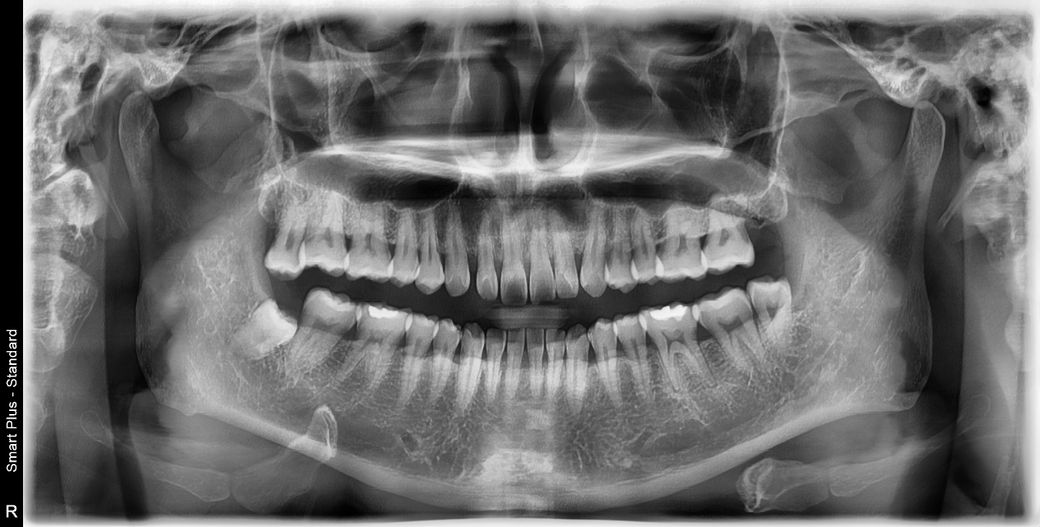

엑스레이 만으로도 임플란트시에 뼈이식 해야 하는지 여부는 알 수있다고 해서 궁금해서 올려봅니다.

왼쪽 어금니 아말감 인레인 한 부분 크랙 때문에 제거하고 신경치료 중입니다. 크랙이 좀 깊어서 일단 크라운 치료 이후에 예후가 안좋을 경우 발치하고 임플란트 해야 한다고 하더라구요. 그런데 임플란트의 경우 뼈이식 하지 않아도 되는 상황이면, 발치후에 바로 식립한다고 하는데 맞는지 궁금하고, 저 같은 경우에는 뼈이식 하지 않고 임플란트 가능한지 궁금하네요.

엑스레이 상으로 보면 특별히 뼈이식을 해야될부분은 없는것 같습니다. 발치하시고 임플란트 하시면될것같습니다.

뼈이식은 필요 없는 상황으로 보이며 발치 후에 바로 임플란트를 하는 것은 치과의사마다 생각이 달라 정해진 건 없습니다.

임플란트 식립 시 뼈 이식의 경우 파노라마 또는 ct 사진상에서 길이를 재봐야 알 수 있습니다 사진상으로는 특별히 뼈가 부족해보이지는 않습니다